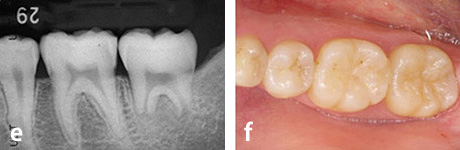

先天的小臼歯欠損部への親知らずの移植

17歳、少女。左下の第二小臼歯が生まれつきありません。そこで、右下親知らずの移植を行いました。この症例では、左下の親知らずでもドナー歯として大丈夫ですが、抜歯しやすい右下を選びました。

治療前。

乳歯がまだ残っています。

移植直後

移植後8ヶ月

移植後3年

移植後6年